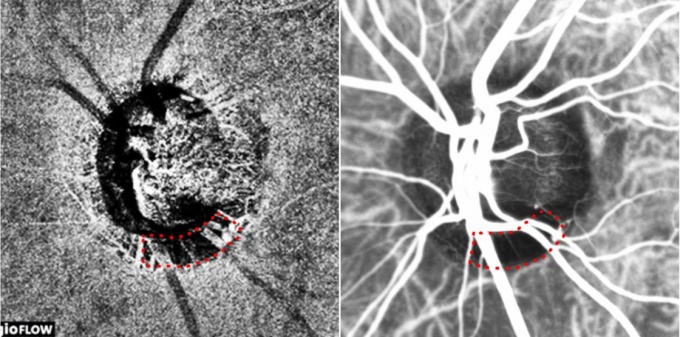

ºÐ´ç¼­¿ï´ëº´¿ø ¾È°ú ±èÅ¿ì, ÀÌÀºÁö ±³¼öÆÀÀÌ ³ì³»ÀåÀÇ ¿øÀÎÀÌ µÇ´Â ½Ã½Å°æ ÁÖº¯ÀÇ ¸Æ¶ô¸· Ç÷·ù ÀúÇϸ¦ ºñħ½ÀÀûÀÎ °Ë»ç¹ýÀ» ÅëÇØ Á¤È®ÇÏ°Ô °üÂûÇÒ ¼ö ÀÖ´Ù´Â »ç½ÇÀ» ¼¼°è ÃÖÃÊ·Î ÀÔÁõÇß´Ù°í 4ÀÏ ¹àÇû´Ù.

ÃÖ±Ù ÀÎü Á¶Á÷ÀÇ ´Ü¸é¿µ»óÀ» ¾ò´Â ‘ºû°£¼·´ÜÃþÃÔ¿µ’À» ÅëÇØ ºÎÀÛ¿ë ¾øÀÌ ºñħ½ÀÀûÀ¸·Î ¾È±¸ ¹Ì¼¼Ç÷°üÀ» °üÂûÇÒ ¼ö ÀÖ´Â ±â¼úÀÌ °³¹ßµÆ°í ºÐ´ç¼­¿ï´ëº´¿ø ¾È°ú ±èÅ¿ì, ÀÌÀºÁö ±³¼ö ¿¬±¸ÆÀÀÌ ½ÇÁ¦ ÀÓ»ó¿¡¼­ À̸¦ À¯¿ëÇÏ°Ô »ç¿ëÇÒ ¼ö ÀÖÀ½À» ¼¼°è ÃÖÃÊ·Î ÀÔÁõÇß´Ù.

¿¬±¸ÆÀÀº ½Ã½Å°æ Ç÷·ù ÀúÇϸ¦ º¸ÀÎ ³ì³»Àå ȯÀÚ 30¸íÀ» ´ë»óÀ¸·Î ±âÁ¸ÀÇ Ä§½ÀÀû °Ë»çÀÎ Àεµ½Ã¾Æ´Ñ±×¸°(Ư¼ö Çü±¤¹°Áú·Î Á¶¿µÁ¦ÀÇ ÀÏÁ¾) Ç÷°üÁ¶¿µ°Ë»ç¿Í ºû°£¼·´ÜÃþ Ç÷°üÁ¶¿µ°Ë»ç¸¦ ÅëÇØ °¢°¢ °üÂûÇÑ ½Ã½Å°æÀ¯µÎ À̹ÌÁö¸¦ ºñ±³ ºÐ¼®Çß´Ù.

±× °á°ú ½Ã½Å°æ ÁÖÀ§¿¡ ¸Æ¶ô¸· Ç÷·ù°¡ ±¹¼ÒÀûÀ¸·Î °¨¼ÒÇÑ ¿µ¿ªÀÌ µÎ °Ë»ç¿¡¼­ ÀÏÄ¡ÇÑ´Ù´Â »ç½ÇÀ» ¹ß°ßÇß´Ù. ÀÌ´Â ³ì³»Àå ȯÀÚÀÇ ½Ã½Å°æ Ç÷·ù ÀúÇϸ¦ °üÂûÇϴµ¥ ÀÖ¾î ºñħ½ÀÀû °Ë»ç¹ýÀÌ ±âÁ¸ÀÇ Ä§½ÀÀû °Ë»ç ¸øÁö¾Ê°Ô Á¤È®ÇÏ´Ù´Â Àǹ̴Ù.

ºÐ´ç¼­¿ï´ëº´¿ø ¾È°ú ÀÌÀºÁö ±³¼ö´Â "ºû°£¼·´ÜÃþ Ç÷°üÁ¶¿µ°Ë»ç°¡ ±âÁ¸ÀÇ Ä§½ÀÀû °Ë»ç¸¦ ´ëüÇÒ ¼ö ÀÖ´Â Á¤È®ÇÑ °Ë»ç¹ýÀÓÀ» ÃÖÃÊ·Î Áõ¸íÇß´Ù"¸ç "¾ÕÀ¸·Î´Â »õ·Î¿î °Ë»ç¹ýÀ» ÀÌ¿ëÇØ ºÎÀÛ¿ë ¾øÀÌ ¾ÈÀüÇÏ°í ½Å¼ÓÇÏ°Ô ³ì³»Àå ȯÀÚÀÇ ½Ã½Å°æ Ç÷·ù »óŸ¦ ÆÄ¾ÇÇÒ ¼ö ÀÖ°Ô µÆ´Ù"°í ¿¬±¸ Àǹ̸¦ ¼³¸íÇß´Ù.